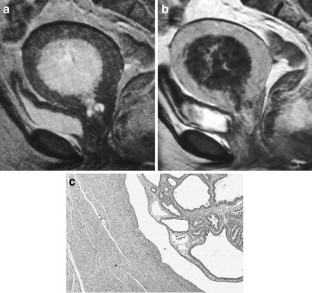

The endometrial cavity may demonstrate various imaging manifestations such as normal, reactive, inflammatory, and benign and malignant neoplasms. We evaluated usual and unusual magnetic resonance imaging (MRI) findings of the uterine endometrial cavity, and described the diagnostic clues to differential diagnoses. Surgically proven pathologies of the uterine endometrial cavity were evaluated retrospectively with pathologic correlation. The pathologies included benign endometrial neoplasms such as endometrial hyperplasia and polyp, malignant endometrial neoplasms such as endometrial carcinoma and carcinosarcoma, endometrial–myometrial neoplasm such as endometrial stromal sarcoma, pregnancy-related lesions in the endometrial cavity such as gestational trophoblastic diseases (hydatidiform mole, invasive mole and choriocarcinoma) and placental polyp, myometrial lesions simulating endometrial lesions such as submucosal leiomyoma and some adenomyosis, endometrial neoplasms simulating myometrial lesions such as adenomyomatous polyp and endometrial lesions arising in the hemicavity of a septate/bicornate uterus, and fluid collections in the uterine cavity (hydro/hemato/pyometra). It is important to recognize various imaging findings in these diseases, in order to make a correct preoperative diagnosis.